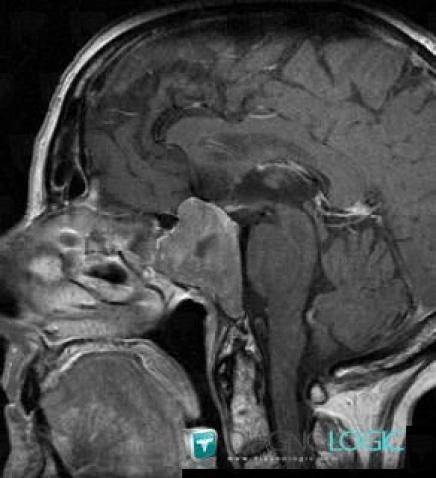

Macroadénome hypophysaire, Hypophyse et région parasellaire, IRM

Voici les informations spécifiques à l'image clé ci dessus:

- Diagnostic Macroadénome hypophysaire, Localisation(s) Hypophyse et région parasellaire, comportant les gammes Lésion en hypersignal T2 sellaire ou parasellaire